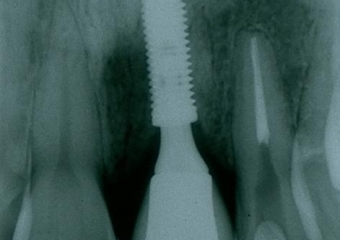

Raio X inicial